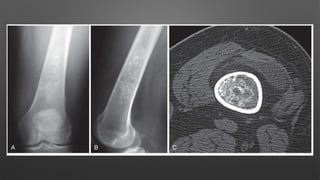

• Presentation

• Symptoms

• pain and swelling

• may present with pathologic fracture

• Physical exam

• neurologic deficits possible with spine lesions

• Imaging

• Radiographs

• expansile, eccentric and lytic lesion with bony

septae ("bubbly appearance")

• usually in metaphyseal

• classic cases have thin rim of periosteal new

bone surrounding lesion

• no matrix mineralization

• MRI or CT scan

• will show multiple fluid lines

• lesion can expand into soft tissue